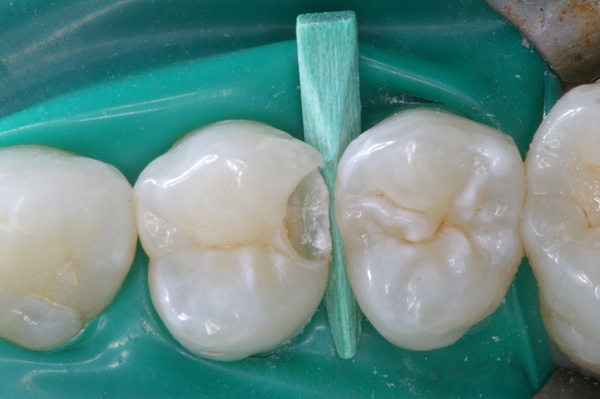

Fig 13. Use of an etch-and-rinse adhesive for the placement of a fiber reinforced composite splint.

Figure 13